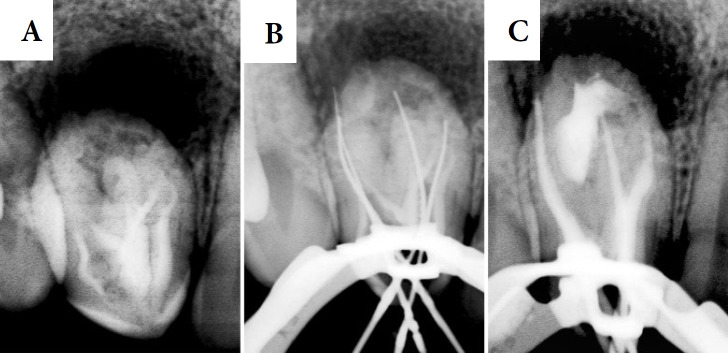

牙凹是一种发育畸形,是由牙釉质器官在组织钙化之前内陷到牙乳头内部区域引起的。本报告的目的是讨论一个临床病例的根管治疗#12牙,使用生物陶瓷封口剂。口腔外检查显示解剖不典型,活力和敲击试验阴性,触诊试验阳性。邻近牙龈黏膜水肿。根据临床和断层检查结果,诊断为牙髓坏死合并慢性根尖周脓肿和Oehlers型牙槽内陷。在第一阶段,在手术显微镜(OM)和超声金刚石尖端的帮助下,使用球形钻头进行手术。找到了四条管道,并对其进行了部分清理和药物治疗。在第二阶段,进行了牙镜测量和镍钛器械化学机械制备。冲洗液为2.5%次氯酸钠。用氢氧化钙糊剂填充根管,暂时封闭根管腔。在第三次治疗中,超声冲洗进行最后的清洗,使用经典的单锥技术用Bio-C密封剂填充根管。在6个月的随访中,牙齿无症状,x线摄影显示明显的骨修复。结论采用断层扫描、手术显微镜、超声冲洗、生物陶瓷封口剂等流量较大的材料,提高了临床病例的成功率。

Dens invaginatus is a developmental malformation that is caused by the invagination of the enamel organ into the internal region of the dental papilla before tissue calcification. The aim of the present report is to discuss a clinical case of endodontic treatment of tooth #12, using bioceramic sealer. The extraoral examination revealed atypical anatomy, while vitality and percussion tests were negative, palpation test was positive. Edema was observed in the adjacent gingival mucosa. Based on clinical and tomographic findings, the diagnosis was pulp necrosis with chronic periapical abscess and Oehlers' type II dens invaginatus. In the first session, access surgery was performed with spherical drills with the aid of an operating microscope (OM) and an ultrasonic diamond tip. Four canals were located, and they were partially debrided and medicated. In the second session, odontometry and chemical-mechanical preparation with nickel-titanium instruments were performed. The irrigation solution was 2.5% sodium hypochlorite. The root canals were filled with calcium hydroxide paste and the chamber was temporarily sealed. During the third session, ultrasonic irrigation was applied for final washing and the root canals were filled with Bio-C sealer using the classic single-cone technique. At 6-month follow-up, the tooth was asymptomatic and the radiography revealed significant bone repair. It was concluded that tomography, operating microscope, ultrasonic irrigation, and materials with greater flow, such as bioceramic sealers, enhanced the clinical success of the clinical case.